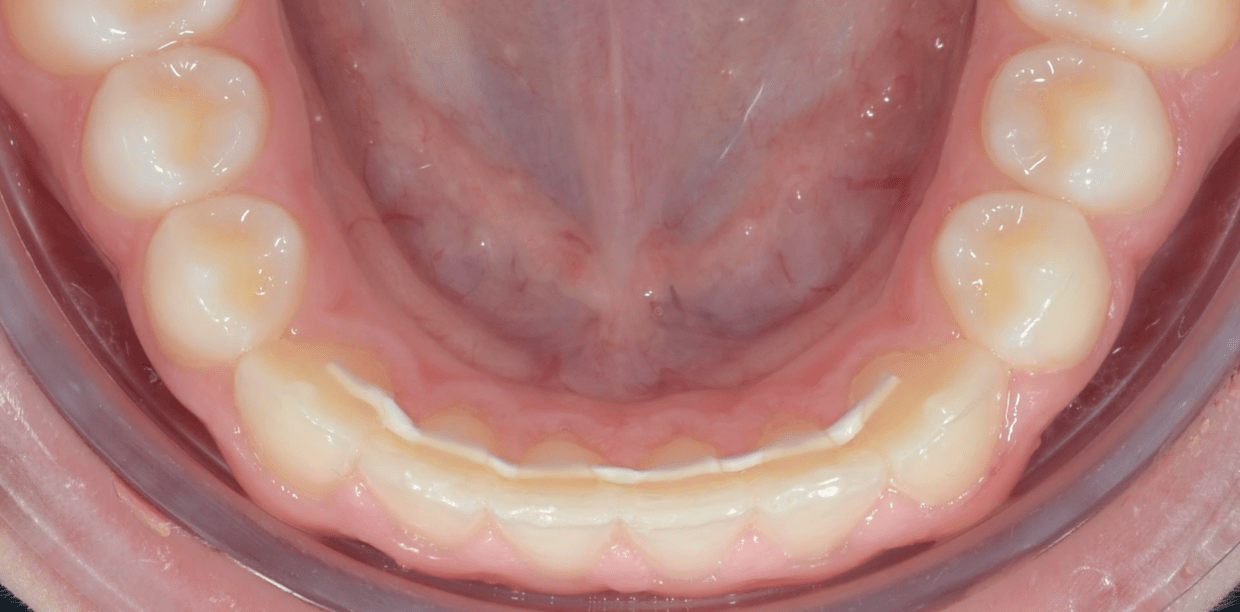

Cas cliniques

Simple - White

Simple - White

Simple - White